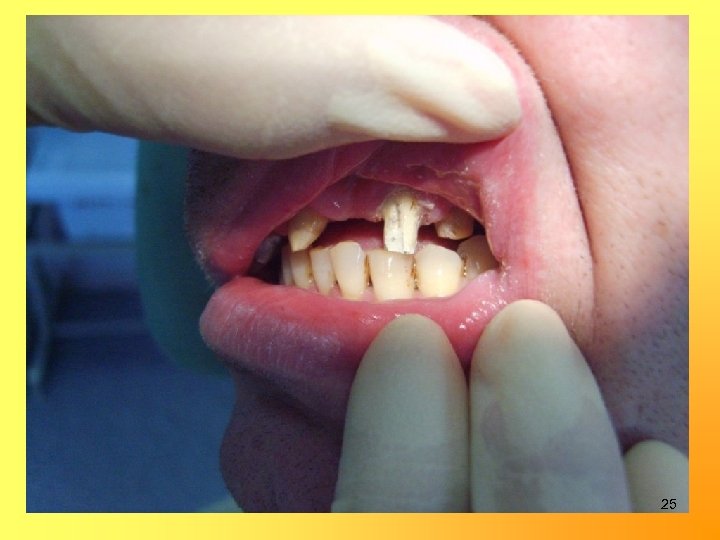

Изготовление металлокерамических мостовидных протезов и коронок 1, 5 -2, 0 мм 1, 0 -1, 5 мм 1, 0 мм 24

25